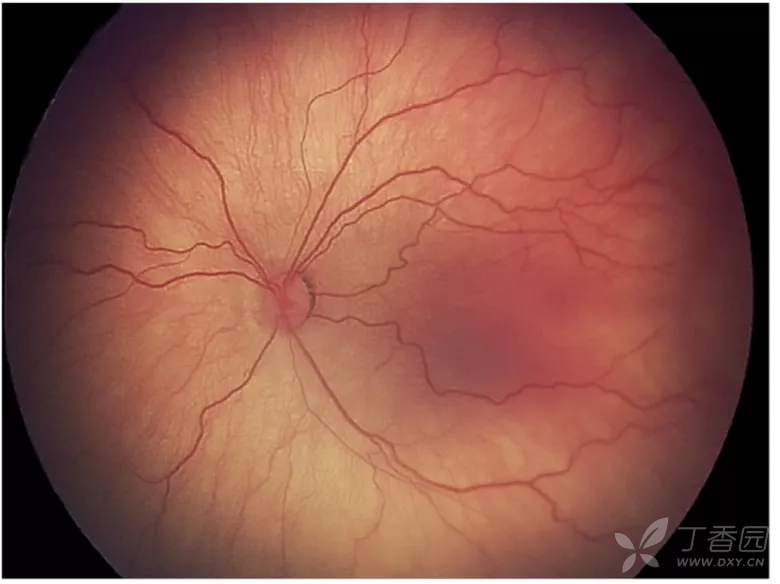

02、plus病变和plus病变前期

plus病变指视网膜血管扩张和迂曲。plus病变前期定义为视网膜血管异常扩张和迂曲,但不足以诊断为plus病变。

图. 轻度plus病变前期,较正常更明显的动脉迂曲和静脉扩张。